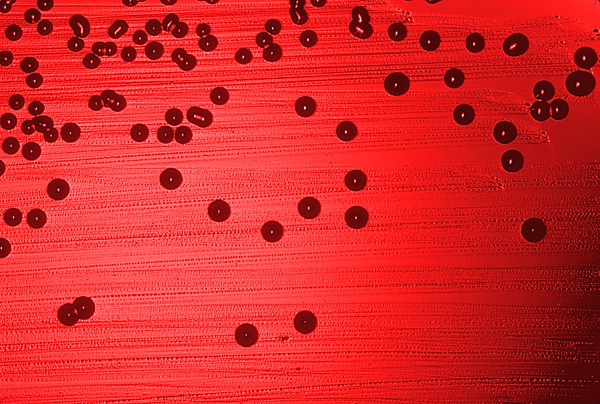

Хемоорганогетеротроф, факультативный анаэроб. Образует маленькие, непрозрачные плоские колонии на средах, содержащих прогретую кровь (кровяной агар только с лошадиной или кроличьей кровью, шоколадный агар, Колумбийский агар и среда Левенталя обогащённые гемоглобином), не растёт на простых питательных средах, не содержащих кровь. Для жизнедеятельности необходимы факторы роста X и V, зависимость от которых является систематическим признаком[2]. Сбраживает глюкозу с образованием кислоты. Образует колонии S- и R- типа. Гладкие колонии S- типа образуются H. influenzae типа b, образующих капсулу.

Для гемофильных бактерий характерен так называемый феномен кормушки или сателлита, который проявляется в их способности расти на кровяном агаре вокруг колоний стафилококков или других бактерий, продуцирующих НАД или вызывающих гемолиз. Для самих гемофильных палочек, способность вызывать гемолиз не характерна. Мелкие радужные колонии гемофильных бактерий могут быть обнаружены на кровяном агаре только в зоне гемолиза, образуемой другими микроорганизмами, например стафилококками.